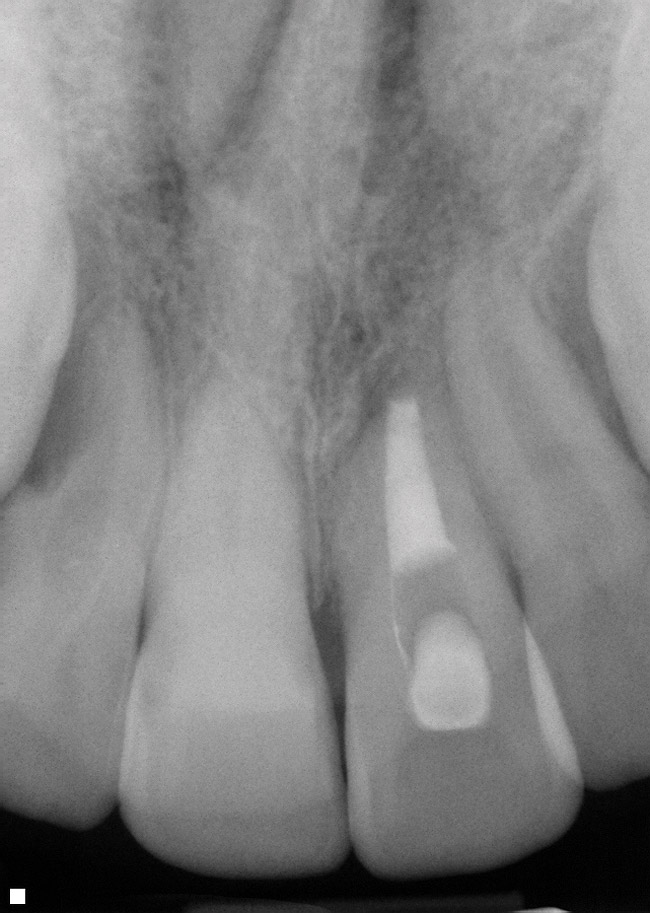

As mentioned, all risk factors associated with both root canal and implant therapy must be carefully considered. Comprehensive clinical and radiographic assessments are necessary to evaluate the patient's risk factors associated with his or her particular case (Figure 1, Figure 2 and Figure 3). The primary risk factors for implants can include smoking, bone quality, and systemic health. For endodontic therapy the primary risk factors are related to the anatomic root complexity, failed root canal treatment with significant technical defects manifested as iatrogenic events, less-than-optimal periodontal status of the tooth (due to a subsequent risk of vertical fracture), and a clinician's lack of experience with regard to the case's complexity. A strong correlation exists between failed root canal treatment and a lack of coronal seal after treatment. This is highly relevant in treatment planning. Often, endodontically treated teeth fail not because they were treated inappropriately and need extraction, but rather, because they have been left unsealed and assaulted by bacteria after the endodontic therapy, causing subsequent long-term clinical failure (Figure 4 and Figure 5).

While not elaborated on here, it is noteworthy that there are a number of additional treatments for resorption that have been suggested in the literature, including calcitonin,27 Emdogain,24,28 and Alendronate (third-generation bisphosphonate in treating EIRR)29 (Figure 6, Figure 7, Figure 8, Figure 9, Figure 10, Figure 11, Figure 12, Figure 13, Figure 14 and Figure 15).